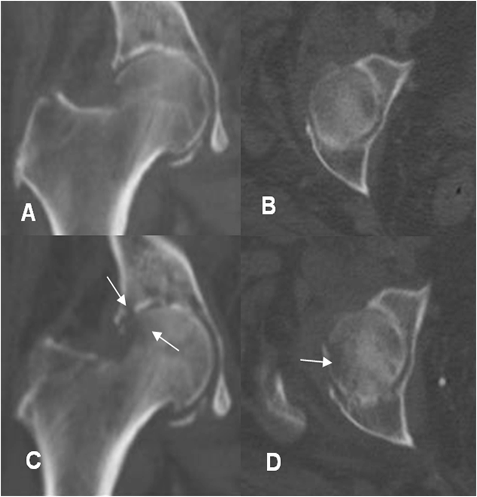

Fig 57 B. Evolución artritis.

A: TAC reconstrucción coronal y B: TAC axial. Disminución del espacio articular y esclerosis del reborde acetabular.

C: TAC reconstrucción coronal y D: TAC axial. Clínica de dolor y limitación funcional. Después de 2 semanas de evolución se identifican lesiones líticas en la cabeza femoral y cavidad acetabular y pérdida del espacio articular, por artritis séptica.